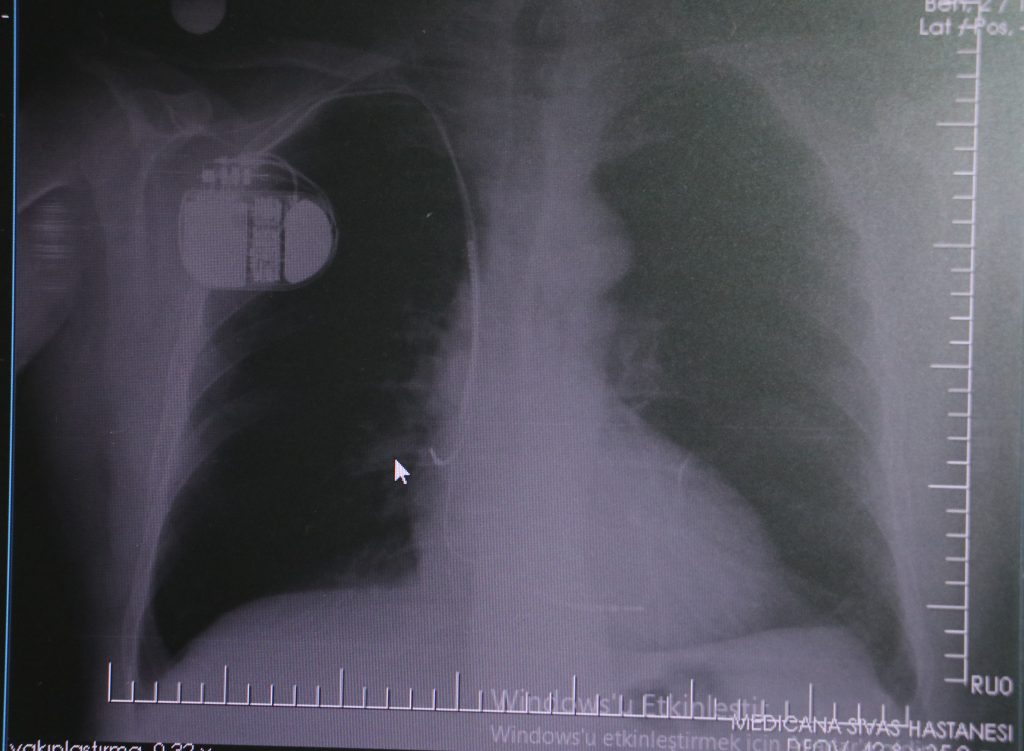

Sivas Medicana Hastanesi Kardiyoloji Uzmanı Dr. İsmail Erdoğu, özellikle kalp pili tedavisinin ani ölümleri önlemede büyük rol oynadığını belirterek, soğuk havalarda kalp pili kullanan hastaların dikkatli olması gerektiği konusunda uyarılarda bulundu.

SİVAS MEDİCANA HASTANESİ KARDİYOLOJİ UZMANI DR. İSMAİL ERDOĞU, ÖZELLİKLE KALP PİLİ TEDAVİSİNİN ANİ ÖLÜMLERİ ÖNLEMEDE BÜYÜK ROL OYNADIĞINI BELİRTEREK, SOĞUK HAVALARDA KALP PİLİ KULLANAN HASTALARIN DİKKATLİ OLMASI GEREKTİĞİ KONUSUNDA UYARILARDA BULUNDU. (SANCAR ALP FIRAT/SİVAS-İHA) Sivas Medicana Hastanesi Kardiyoloji Uzmanı Dr. İsmail Erdoğu, özellikle kalp pili tedavisinin ani ölümleri önlemede büyük rol oynadığını belirterek, soğuk havalarda kalp pili kullanan hastaların dikkatli olması gerektiği konusunda uyarılarda bulundu.

Konuya ilişkin açıklamalarda bulunan Sivas Medicana Hastanesi Kardiyoloji Bölümü Uzmanı Dr. İsmail Erdoğu, kalp pilinin önemine vurgu yaptı. Erdoğu, Yeni nesil kalp pillerinin MR cihazlarına girmeye imkan sağladığı, ancak tarama cihazlarından geçmenin önerilmediğini ifade ederek,

“Soğuk hava nedeniyle oluşan titremeler, kalp pilinin kalbin durduğunu sanmasına ve yanlış şoklamaya yol açabilir. Bu nedenle hastalarımızın bu dönemlerde daha dikkatli olmalarını öneriyoruz”

dedi.

“Çok büyük bir ameliyat değil ama yine de ciddi bir cerrahi işlem. Kalp pili, tıpta son 30 yılda yaşanan gelişmelerden en büyüğü. Bir bilgisayarın küçültülüp insan vücuduna konulmuş hali aslında. İnsan ömrünü ciddi oranda uzatan bir tedavi. İnsanlar bir şokla hayata tutunurken, pil olmasaydı öleceğini düşündüğümüz birçok hastamız var. Kalp pilinin bu özelliği, uygun hastalarda ciddi oranda ani ölümü engelliyor. Hastanın başına gelecek bir kalp durması durumunda yanında bir sağlıkçı yoksa, onun ritmini düzeltecek defibrilatör cihazı yoksa hastayı hayatta tutmak mümkün değil. Uygun endikasyonlarda kalp pili olduğu zaman, pil hastaların ritmini algılıyor ve acilde yapılan şoklamayı yaparak hastayı hayata döndürüyor. Kalp pillerinde yeni teknolojilerle MR’a girmek mümkün, tomografiye zaten girebiliyorlar. Tarama cihazlarından geçmelerini uygun görmüyoruz. Bu tarz durumlarda hastalarımız ‘kalp pilim var’ dediğinde muaf tutuluyorlar. Kalp pilleri ciddi teknolojik cihazlardır. Vücudun içindeki titreşimi, örneğin mikser kullanmak, kolunu sallayacak herhangi bir eylem kalp pilinde olumsuz etki oluşturabilir. Soğuk havalarda vücutta oluşan ciddi titremeler kalp pilinin hafızasını karıştırıp kalbin durduğunu düşündürebilir ve gereksiz şoklama yapabilir. Bu tarz kişilerin soğuk havalarda daha temkinli olması gerekir”